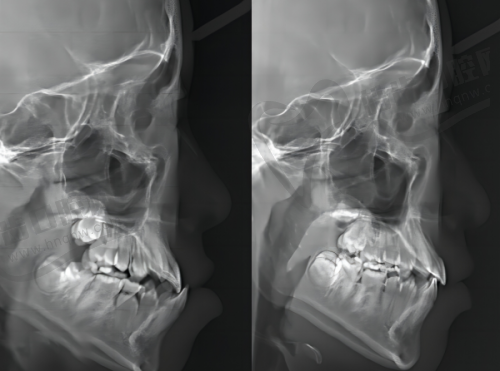

医生的修复技术水平对树脂牙贴面的使用年限起着至关重要的作用。经验多、技术不错的医生,在进行牙齿贴面修复时,能够正确地把握牙齿的形态和位置,将贴面贴合得更加紧密、牢固。

他们会对牙齿表面进行适当的处理,确保贴面与牙齿之间有良好的粘结力,这样可以减少贴面脱落的风险。而且在操作过程中,能够避免对牙齿造成不必要的损伤,有利于维持牙齿的健康。

相反,如果医生技术不过关,在贴合贴面时不够精细,或者粘结不牢固,就容易导致贴面在使用过程中出现松动、脱落等问题,大大缩短了树脂牙贴面的使用年限。所以在选择医生时,要尽量选择有丰富经验和良好口碑的牙齿修复医生。